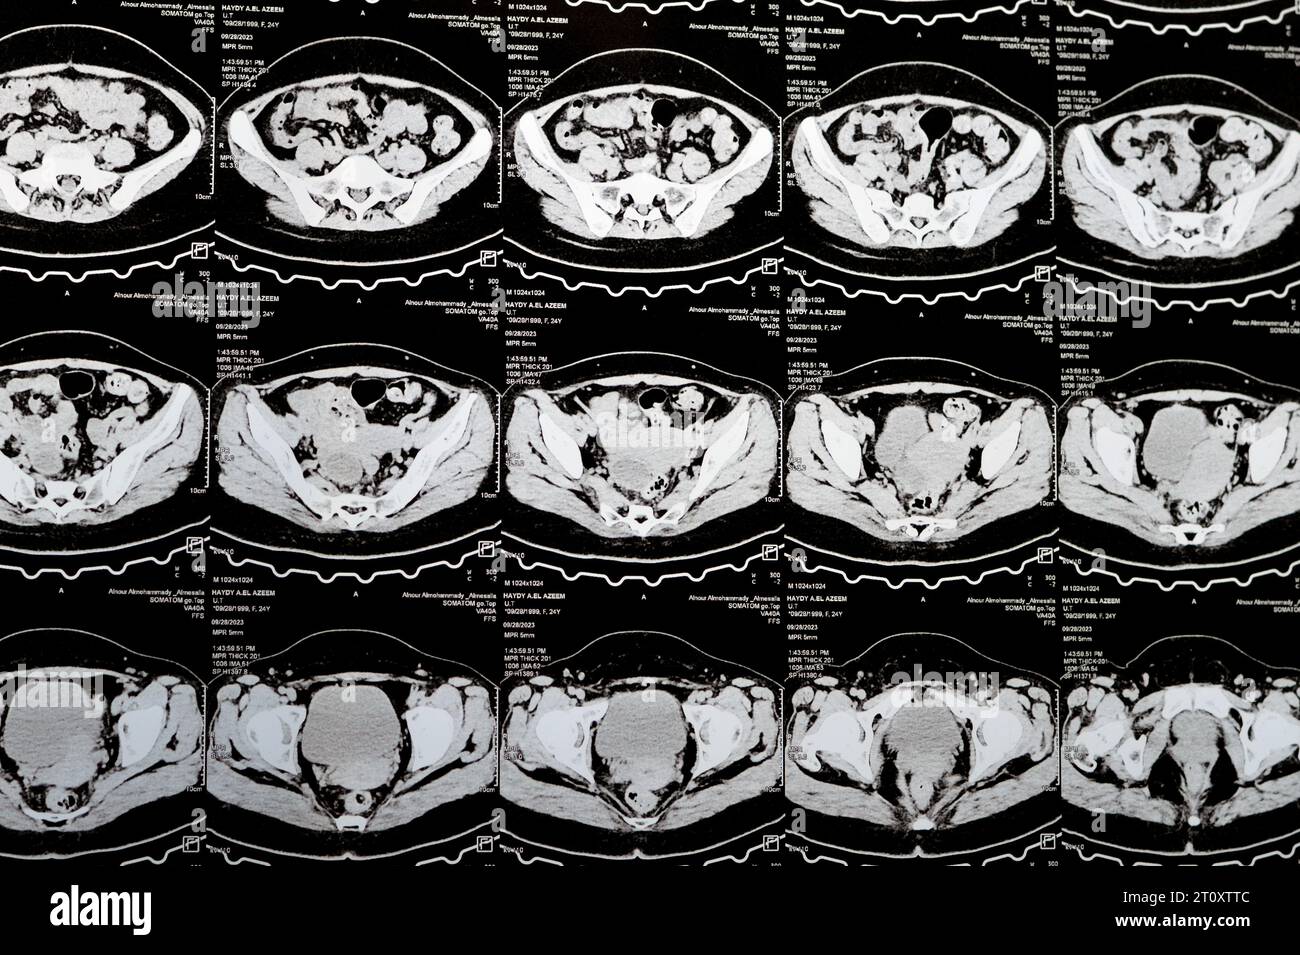

Le Caire, Égypte, octobre 3 2023 : le scanner multi-coupes de l'abdomen et du bassin montre un kyste de l'ovaire droit de 3 x 3 cm, une distension gazeuse colique, pas d'urine importante Banque D'Imageshttps://www.alamyimages.fr/image-license-details/?v=1https://www.alamyimages.fr/le-caire-egypte-octobre-3-2023-le-scanner-multi-coupes-de-l-abdomen-et-du-bassin-montre-un-kyste-de-l-ovaire-droit-de-3-x-3-cm-une-distension-gazeuse-colique-pas-d-urine-importante-image568526222.html

Le Caire, Égypte, octobre 3 2023 : le scanner multi-coupes de l'abdomen et du bassin montre un kyste de l'ovaire droit de 3 x 3 cm, une distension gazeuse colique, pas d'urine importante Banque D'Imageshttps://www.alamyimages.fr/image-license-details/?v=1https://www.alamyimages.fr/le-caire-egypte-octobre-3-2023-le-scanner-multi-coupes-de-l-abdomen-et-du-bassin-montre-un-kyste-de-l-ovaire-droit-de-3-x-3-cm-une-distension-gazeuse-colique-pas-d-urine-importante-image568526222.htmlRF2T0XGYX–Le Caire, Égypte, octobre 3 2023 : le scanner multi-coupes de l'abdomen et du bassin montre un kyste de l'ovaire droit de 3 x 3 cm, une distension gazeuse colique, pas d'urine importante

Le Caire, Égypte, octobre 3 2023 : le scanner multi-coupes de l'abdomen et du bassin montre un kyste de l'ovaire droit de 3 x 3 cm, une distension gazeuse colique, pas d'urine importante Banque D'Imageshttps://www.alamyimages.fr/image-license-details/?v=1https://www.alamyimages.fr/le-caire-egypte-octobre-3-2023-le-scanner-multi-coupes-de-l-abdomen-et-du-bassin-montre-un-kyste-de-l-ovaire-droit-de-3-x-3-cm-une-distension-gazeuse-colique-pas-d-urine-importante-image568533363.html

Le Caire, Égypte, octobre 3 2023 : le scanner multi-coupes de l'abdomen et du bassin montre un kyste de l'ovaire droit de 3 x 3 cm, une distension gazeuse colique, pas d'urine importante Banque D'Imageshttps://www.alamyimages.fr/image-license-details/?v=1https://www.alamyimages.fr/le-caire-egypte-octobre-3-2023-le-scanner-multi-coupes-de-l-abdomen-et-du-bassin-montre-un-kyste-de-l-ovaire-droit-de-3-x-3-cm-une-distension-gazeuse-colique-pas-d-urine-importante-image568533363.htmlRF2T0XX2Y–Le Caire, Égypte, octobre 3 2023 : le scanner multi-coupes de l'abdomen et du bassin montre un kyste de l'ovaire droit de 3 x 3 cm, une distension gazeuse colique, pas d'urine importante

Le Caire, Égypte, octobre 3 2023 : le scanner multi-coupes de l'abdomen et du bassin montre un kyste de l'ovaire droit de 3 x 3 cm, une distension gazeuse colique, pas d'urine importante Banque D'Imageshttps://www.alamyimages.fr/image-license-details/?v=1https://www.alamyimages.fr/le-caire-egypte-octobre-3-2023-le-scanner-multi-coupes-de-l-abdomen-et-du-bassin-montre-un-kyste-de-l-ovaire-droit-de-3-x-3-cm-une-distension-gazeuse-colique-pas-d-urine-importante-image568532396.html

Le Caire, Égypte, octobre 3 2023 : le scanner multi-coupes de l'abdomen et du bassin montre un kyste de l'ovaire droit de 3 x 3 cm, une distension gazeuse colique, pas d'urine importante Banque D'Imageshttps://www.alamyimages.fr/image-license-details/?v=1https://www.alamyimages.fr/le-caire-egypte-octobre-3-2023-le-scanner-multi-coupes-de-l-abdomen-et-du-bassin-montre-un-kyste-de-l-ovaire-droit-de-3-x-3-cm-une-distension-gazeuse-colique-pas-d-urine-importante-image568532396.htmlRF2T0XTTC–Le Caire, Égypte, octobre 3 2023 : le scanner multi-coupes de l'abdomen et du bassin montre un kyste de l'ovaire droit de 3 x 3 cm, une distension gazeuse colique, pas d'urine importante

Le Caire, Égypte, octobre 3 2023 : le scanner multi-coupes de l'abdomen et du bassin montre un kyste de l'ovaire droit de 3 x 3 cm, une distension gazeuse colique, pas d'urine importante Banque D'Imageshttps://www.alamyimages.fr/image-license-details/?v=1https://www.alamyimages.fr/le-caire-egypte-octobre-3-2023-le-scanner-multi-coupes-de-l-abdomen-et-du-bassin-montre-un-kyste-de-l-ovaire-droit-de-3-x-3-cm-une-distension-gazeuse-colique-pas-d-urine-importante-image568507925.html

Le Caire, Égypte, octobre 3 2023 : le scanner multi-coupes de l'abdomen et du bassin montre un kyste de l'ovaire droit de 3 x 3 cm, une distension gazeuse colique, pas d'urine importante Banque D'Imageshttps://www.alamyimages.fr/image-license-details/?v=1https://www.alamyimages.fr/le-caire-egypte-octobre-3-2023-le-scanner-multi-coupes-de-l-abdomen-et-du-bassin-montre-un-kyste-de-l-ovaire-droit-de-3-x-3-cm-une-distension-gazeuse-colique-pas-d-urine-importante-image568507925.htmlRF2T0WNJD–Le Caire, Égypte, octobre 3 2023 : le scanner multi-coupes de l'abdomen et du bassin montre un kyste de l'ovaire droit de 3 x 3 cm, une distension gazeuse colique, pas d'urine importante